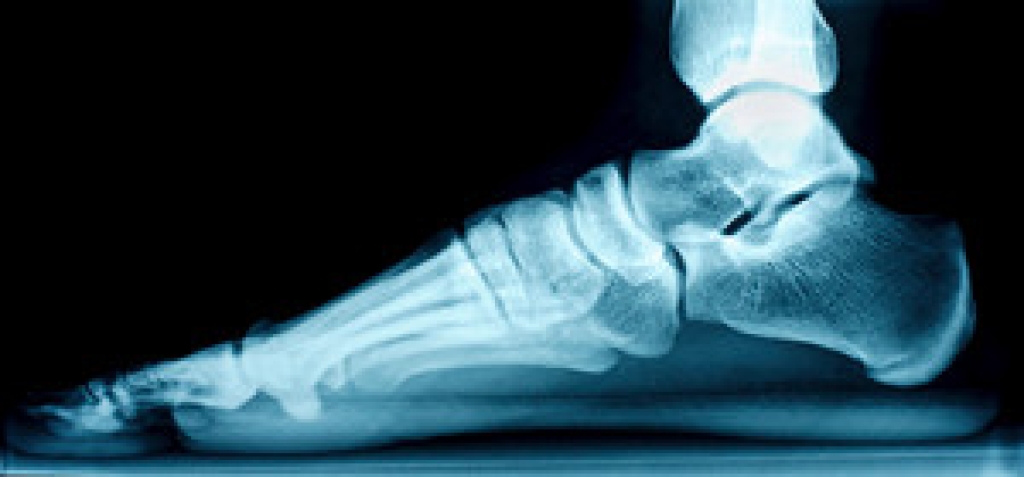

Hammertoe

Hammertoe is a foot deformity that affects the joints of the second, third, fourth, or fifth toes of your feet. It is a painful foot condition in which these toes curl and arch up, which can often lead to pain when wearing footwear.